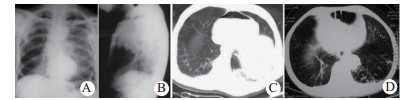

| 图 1 术前X线和CT诊断(A、B:例1张力性心包积气; C:例2血气心包; D:例3心包膈疝) Fig 1 Preoperative X-ray and CT diagnosis (A and B: case 1, tension pneumopericardium; C: case 2, hemopenumopericardium; D: case 3, pericardial diaphragmatic hernia) |